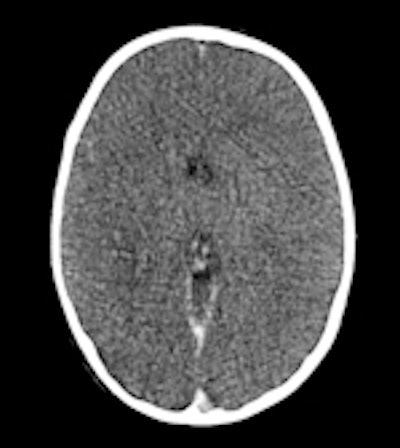

Ci-dessus: cet enfant a été retrouvé mort dans son lit; un scanner et un IRM post mortem ont été effectués un jour après l'heure du décès.

A gauche: scanner conventionnel, épaisseur de coupe de 5mm. A cause de la décomposition, il peut être difficile de différencier la matière grise et la substance blanche, même un jour après l'heure du décès. Au milieu: image 3D, rendu volumique. Cette technique permet dans certains cas de mieux maîtriser les changements post mortem dans l'atténuation cérébrale, mais il reste difficile de différencier les divers tissus cérébraux. Aucune pathologie n'a pu être détectée. A droite: l'IRM (séquence T2) offre une meilleure différentiation entre les divers tissus cérébraux. Si le corps a une température d'à peu près 10° C, les images IRM peuvent être assez bruyantes. Après le scanner et l'IRM, le syndrome de l'enfant battu a été exclu.Répondant aux questions des radiologues français, elle a expliqué que la technique pouvait être appliquée à des cadavres en état avancé de décomposition, du fait de la résistance surprenante des artères à la putréfaction. Son groupe a ainsi appliqué avec succès cette technique sur des cadavres au préalable gelés.